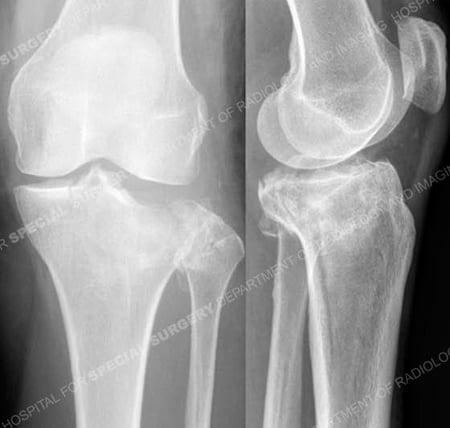

Anteroposterior and lateral radiographs revealing a Schatzker II tibial plateau fracture.

Schatzker II tibial plateau fracture

A 61-year old female was hiking in the mountains when she slipped and fell onto her left lower extremity. She was taken to a local hospital and radiographs revealed a left-sided Schatzker II tibial plateau fracture (split with depressed fragment) and she was referred to Dr. David L. Helfet at the Orthopedic Trauma Service at Hospital for Special Surgery one day following her injury for definitive treatment. Open reduction and internal fixation (ORIF) was performed and included elevation of the depressed fragment, placement of bone graft, reduction of the articular surface and metaphyseal extension and placement of a proximal tibia locking plate and screws. She returned for regular follow-up and healed uneventfully. At the time of her latest follow-up visit, 7 months following fracture surgery, she has excellent radiographic and clinical results including a healed tibial plateau fracture in excellent alignment, maintenance of fixation and knee joint space, complete pain resolution, full range of motion and a return to pre-injury activities.